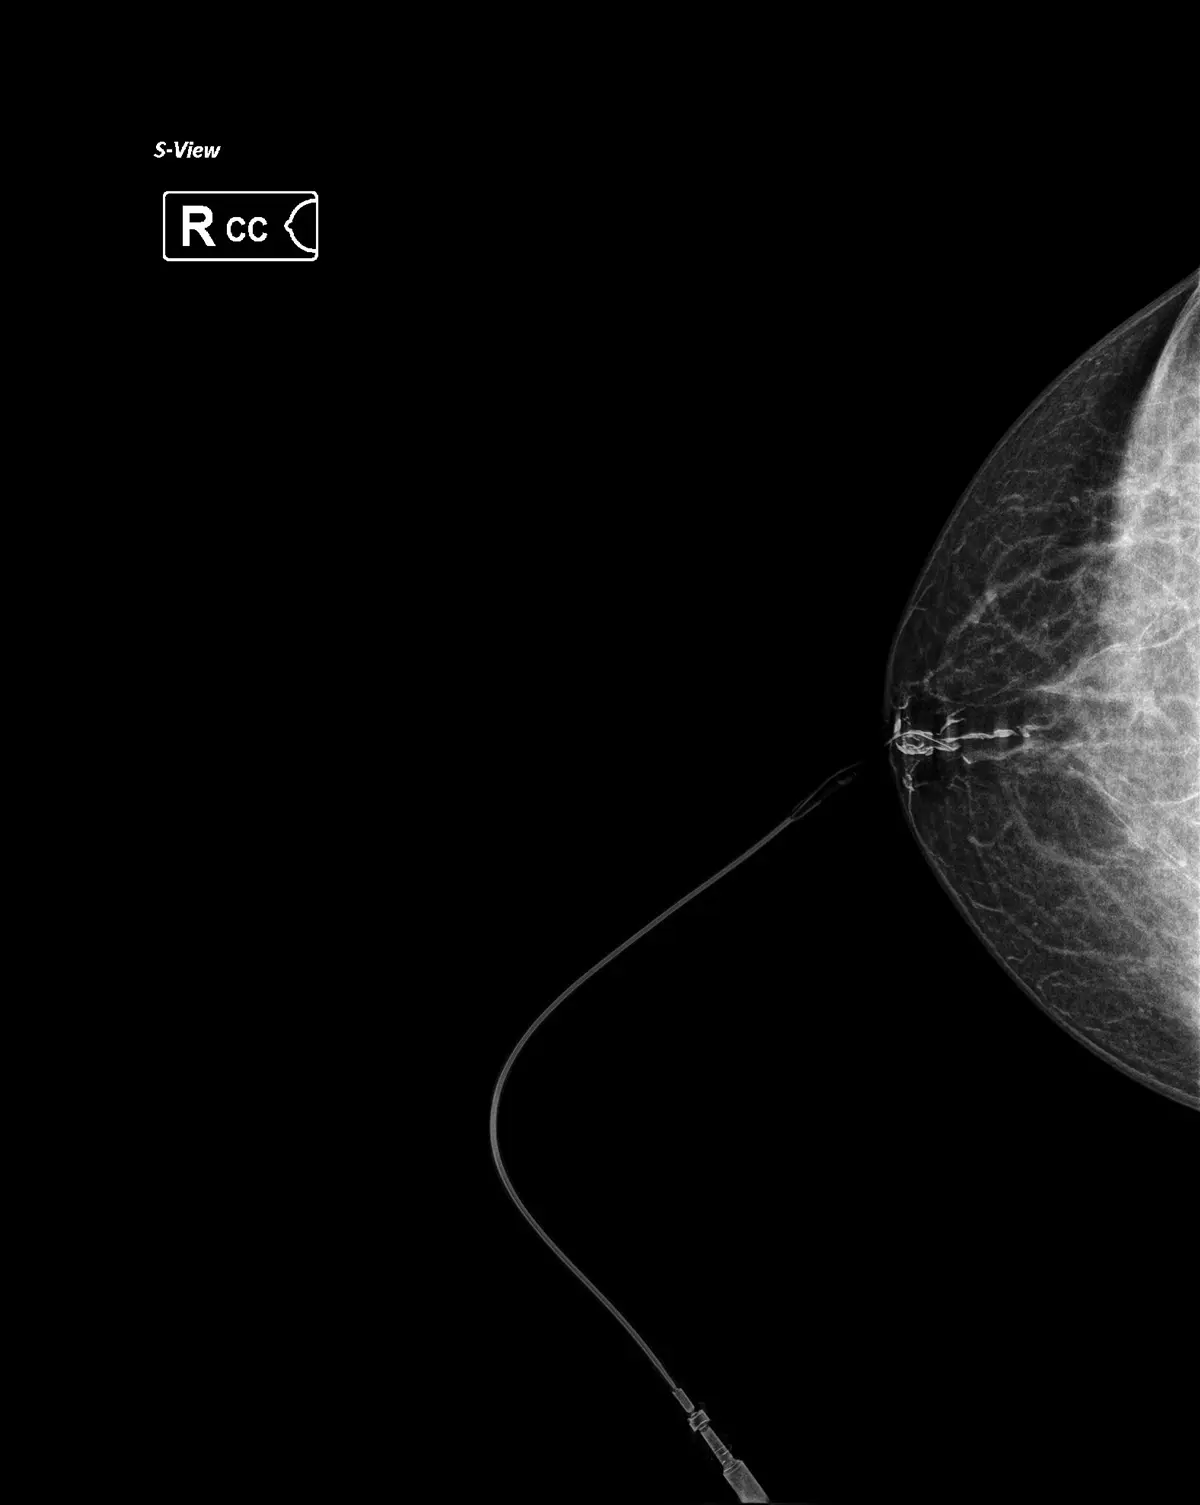

Galaktografija je rendgenska pretraga kod koje se mala količina kontrastnog sredstva aplicira direktno u mliječni kanal iz kojeg dolazi iscjedak, nakon čega se radi ciljana mamografija.

1. Tankim kateterom se aplicira kontrastno sredstvo

2. Radi se ciljana mamografska snimka